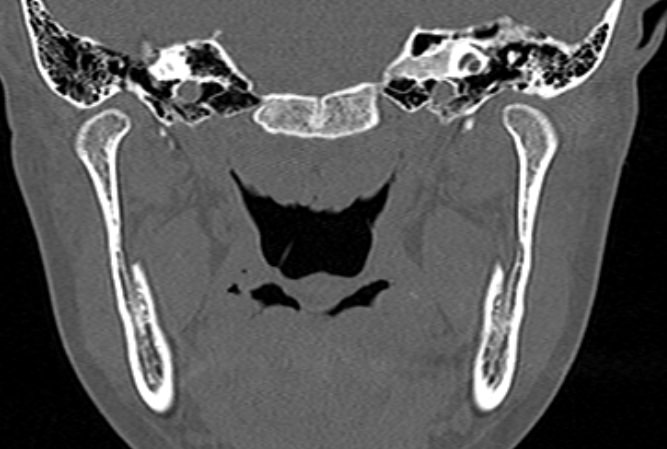

Наиболее точным и информативным методом диагностики костной патологии ВНЧС является мультиспиральная компьютерная томография. КТ относится к лучевым методам исследования, то есть для сканирования применяется рентгеновское излучение. В отличие от обычного рентгена томограф проводит одномоментно множество тончайших срезов исследуемой зоны, которые в дальнейшем проходят цифровую обработку. В результате получаются детальные снимки и трехмерные изображения области височно-нижнечелюстных суставов, которые позволяют проводить точную и достоверную диагностику.

Для оценки функции височно-нижнечелюстных суставов КТ-сканирование проводится в нескольких положениях: с открытым ртом и закрытым ртом. С помощью таких функциональных проб можно оценить положение суставной головки нижней челюсти при движениях нижней челюсти, выявить привычные вывихи и подвывихи суставов.

Компьютерная томография позволяет оценить состояние костных структур височно-нижнечелюстных суставов, так как рентгеновские лучи хорошо задерживаются костной тканью. Для повышения диагностических возможностей компьютерной томографии в ряде случаев дополнительно проводится контрастное усиление путем внутривенного введения йодсодержащего контрастного препарата. Эта методика применяется для улучшения визуализации мягких тканей, которые хуже видны при нативном исследовании.

С помощью КТ можно оценить состояние костной ткани суставных головок нижней челюсти, внутрисуставного мениска, суставной капсулы, связочного аппарата и жевательных мышц.

При проведении мультиспиральной КТ можно выявить следующие патологии височно-нижнечелюстных суставов:

- Травматические повреждения (переломы, вывихи или подвывихи суставов, растяжения связок);

- Воспалительные изменения (артрит височно-нижнечелюстных суставов);

- Дегенеративно-дистрофические заболевания (артроз височно-нижнечелюстных суставов, который проявляется уменьшением просвета внутрисуставной щели, истончением хрящевой ткани, разрастанием остеофитов);